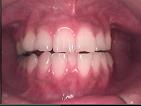

MTM(小矯正)

局所的あるいは比較的軽度の歯列不正に対して実施される矯正治療(歯を動かす治療)です。

通常は矯正はすべて専門医をご紹介しておりますが、たまにやむない事情により実施します。

術前

術中

術後